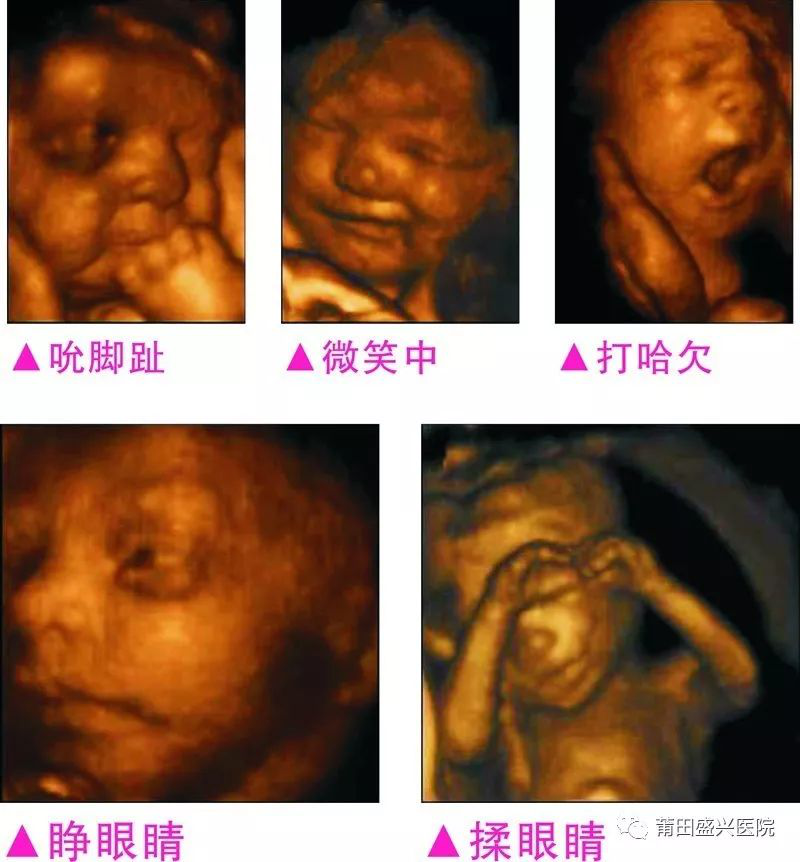

不做四維彩超

您一定不知道寶寶有多調皮可愛(ài)

你一定不知道寶寶這么小就有這么多表情

四維容積成像技術(shù),智能光源系統展現梯度亮度,渲染畫(huà)面,提高容積成像品質(zhì),高清顯示腹中寶寶的實(shí)時(shí)動(dòng)態(tài)影像,完整記錄寶寶的一舉一動(dòng),讓準爸媽與寶寶Di一次幸福“見(jiàn)面”,更可刻錄成高清視頻,送給未來(lái)寶寶的珍貴禮物。